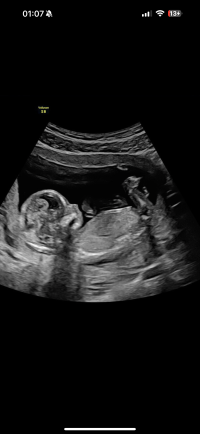

Når man ser lårbeinet kan man dessverre ikke se nub.Er det mulig å se noe nub her? 13+3

Ser lårbenet og da kan man ikke se nun dessverreMulig å se noe her? 14+0 <3

Man ser lårbenet på alle tre, og da kan man ikke se nub dessverreKan man se noe på disse?

Det ene er uke 12+0 og de to siste er 12+5